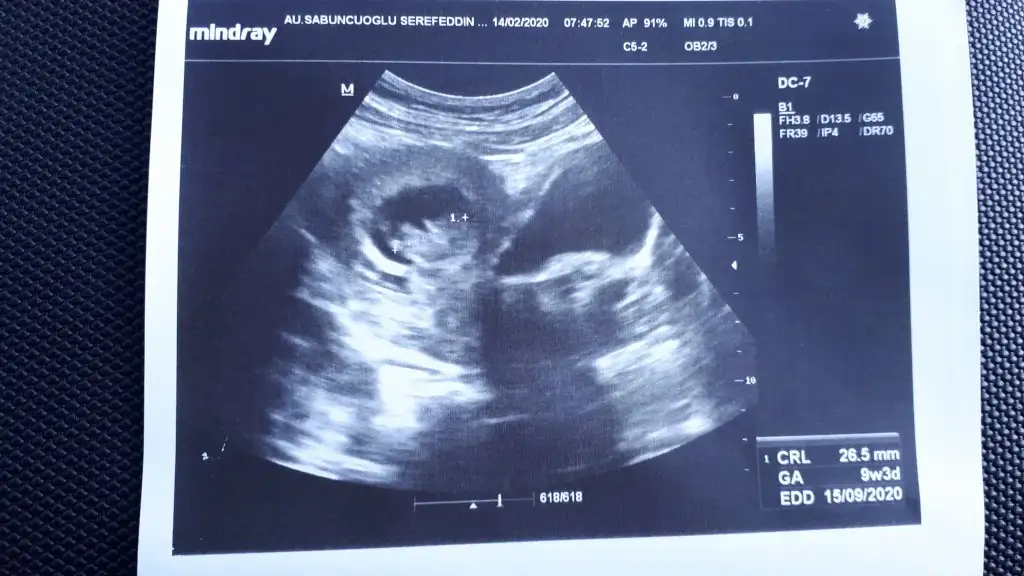

11+ yada 12+ usg paylaşın10. Hafta görüntümüzIkra meyra cinsiyet hakkinda yorum yapabilir misiniz